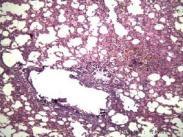

α1抗胰蛋白酶缺乏性肝病

• α1抗胰蛋白酶缺乏性肝病

628健康網(wǎng)為您分享有關(guān)α1抗胰蛋白酶缺乏性肝病的癥狀,α1抗胰蛋白酶缺乏性肝病的治療方法,α1抗胰蛋白酶缺乏性肝病的預(yù)防...